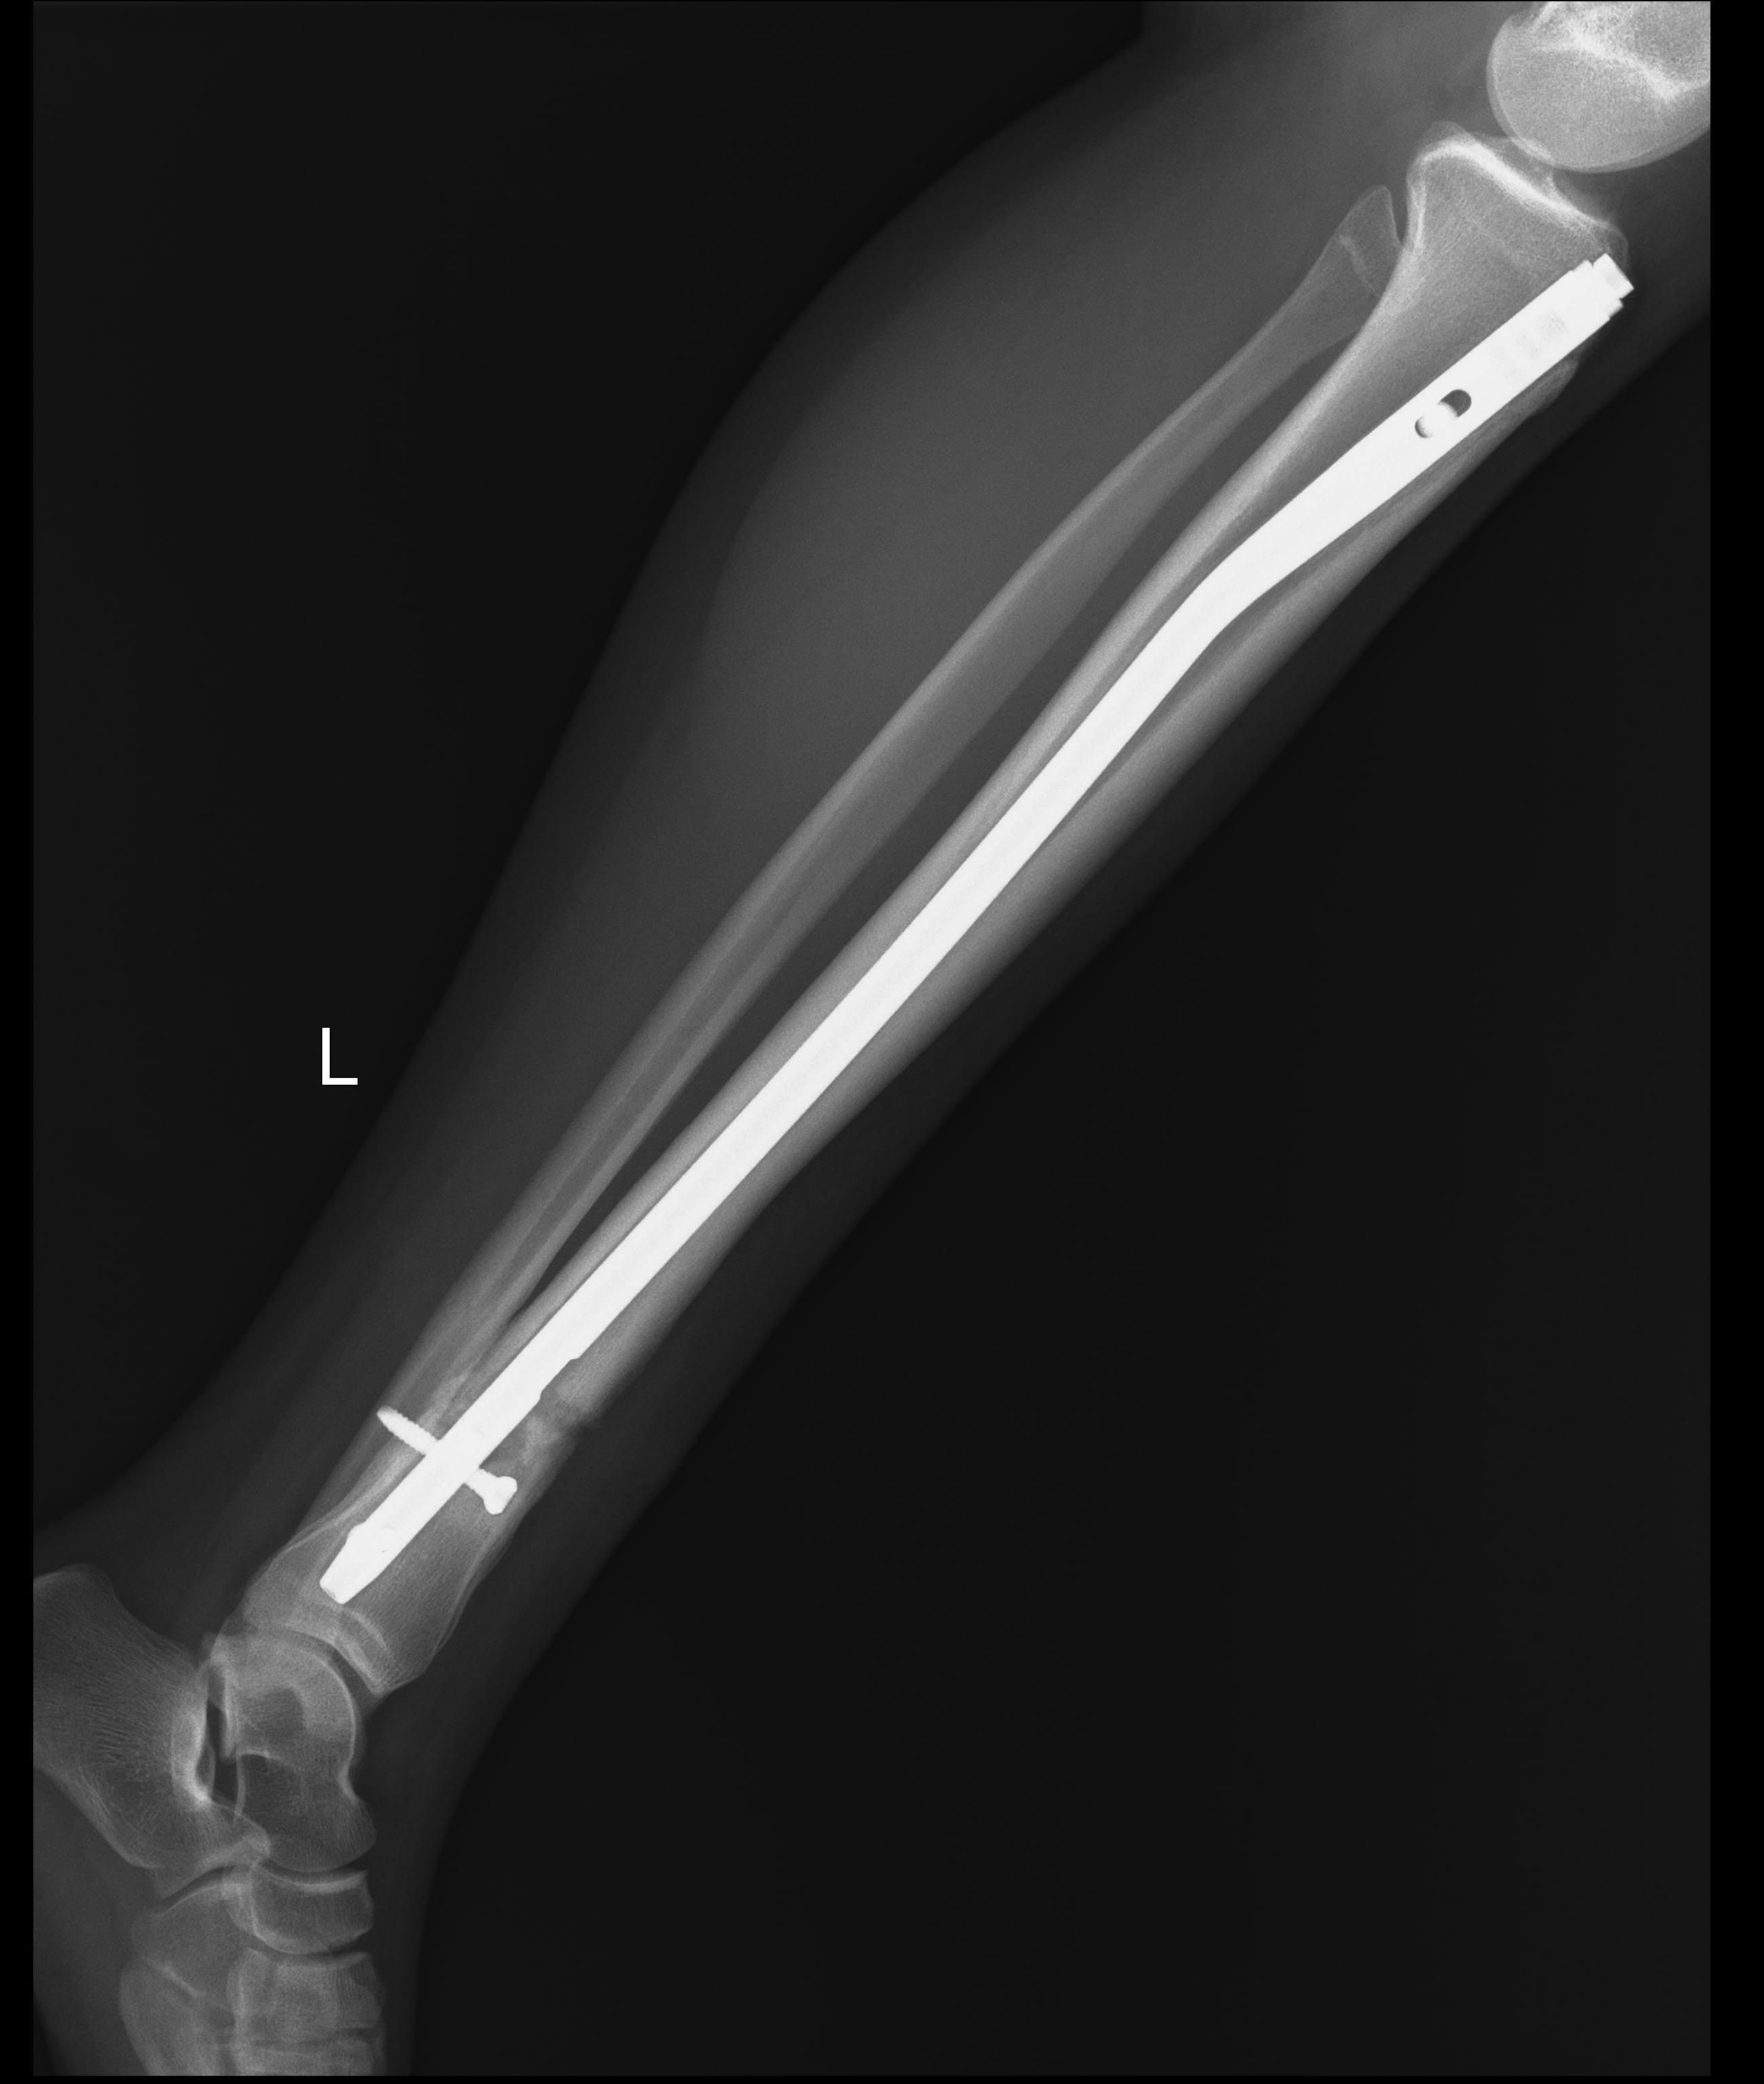

Оригинальные снимки

Репозиция была закрытой. Если детально - был выбран максимально толстый и длинный стержень после римминга канала вручную (9*345мм), но самый обычный, не для дистального метафиза (возможно, и зря). При введении в канал было оценено избыточный варус, вследствии чего стержень удален из дистального отломка и введен после постановки направляющего поллера. Произведено дистальное блокирование, на фоне которого попытка увеличить компрессию частично достигнута выбиванием стержня и проксимальным блокированием. Ввиду ограничения ассортимента длин винтов блокирование было сделано с латеральной стороны, чтобы винты не слишком выступали под кожей.

Удалили все, кроме нижнего, винты. Конечно, сделали остеотомию малоберцовой кости.

"освежили" по Беку зону перелома, ввели PRP

Рекомендована нагрузка до 2 недель на костылях с нарастанием до полной.

Контроль не совсем удачный.

Спасибо за Вашу помощь и поддержку, будем ждать...